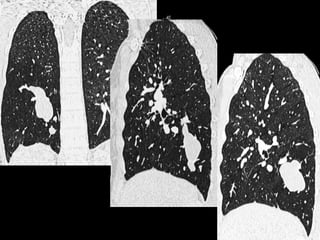

Séquestration intralobaire

Séquestration intralobaire Pneumopathie récidivante chez uneenfant de 20 mois : séquestration intralobaire Hôpital d’enfants CHU Nancy